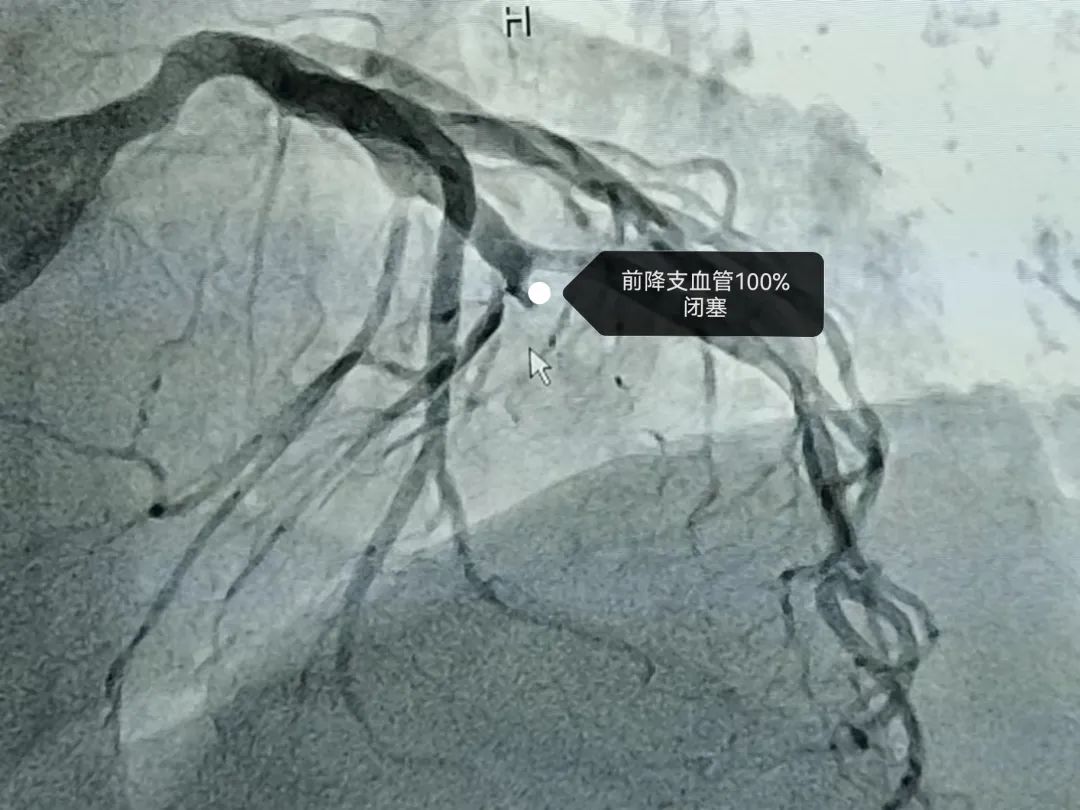

2022年5月4日7点00分家住小河的一位婆婆突感心前区疼痛,伴全身大汗,由于婆婆本身患有冠心病,于是自行服用了“速效救心丸”后胸痛症状稍缓解,可是3小时后婆婆胸痛症状再次发作,程度较前一次更加剧烈,胸痛症状持续不能缓解,在告知家属后立即拨打我院急救120电话,11点15分达到我院急诊科,急诊科医师第一时间通知心内科总住院医师会诊,根据胸痛及心电图表现诊断急性心肌梗死,心脏介入团队随即在导管室集合,11点35分进入导管室开始手术,术中发现冠状动脉最重要的一个分支---前降支完全闭塞,11点50分导丝顺利通过前降支闭塞病变,D to W时间35分钟,并植入支架完全恢复前降支血流,至此,婆婆顺利脱险。